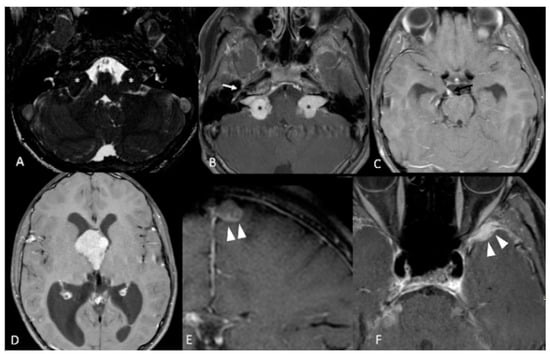

| Vestibular Schwannomas | ~90% | Tinnitus Hearing loss Ataxia | Antoni A, B regions Verocay bodies Hyalinzed vessels | Often bilateral. Slightly T1 hypointense (63%) or isointense (37%). Heterogeneously T2 hyperintense (Antoni A: relatively low, Antoni B: high), cystic degenerative areas may be present if large tumor. Intense contrast enhancement on T1 C+ (Gd) | Radiosurgery Chemotherapy; Bevacizumab | Facial nerve injury Malignant transformation |

| Peripheral Schwannomas -Tumorlets -Plexiform | ~70% | Neuropathic pain Loss of sensation Weakness Tumors on skin, head and neck region (Plexiform) | Antoni A, B regions Verocay bodies Hyalinzed vessels Infiltration of nerve | T1: 75% are isointense, 25% are hypointense. T2: more than 95% are hyperintense, often with mixed signal. Intense contrast enhancement on T1 C+ (Gd) | Intraneural dissection Excision | Rarely undergo malignant transformation although high risk of nerve infiltration |

| Meningiomas | ~50% (20% are in kids) | Headache Seizure | Fibrous morphology Psamomma Bodies High mitotic index | Intense and homogeneous enhancement. Frequent cystic components Can be multiple Present in unusual locations: craniocervical junction. | Surgical excision Radiosurgery Current clinical trial: mTORC1/2 inhibitor AZD2014 (NCT02831257, NCT03071874) | Malignant transformation Invasion to vascular brain structures Compression effect |

| Menigioangiomatosis | rare | Headache Seizures Behavioral changes Cortical blindness Paresis | Plaque like leptomeningeal and perivascular proliferation Fibroblastic and meningothelial appearing cells | Cortical/subcortical white matter mass characterized by Ca⁺⁺, enhancing meningovascular proliferation. Most common in temporal and frontal lobes. | Surgical excision | Intracerebral hemorrhage |

| Glial micro hamartomas | Common | Asymptomatic | Atypical pleomorphic nuclei, Occasional multi-nucleation, Eosinophilic cytoplasm | Cortical hyperintense T2/FLAIR lesions “Transmantle sign” | Surveillance and monitoring | None |